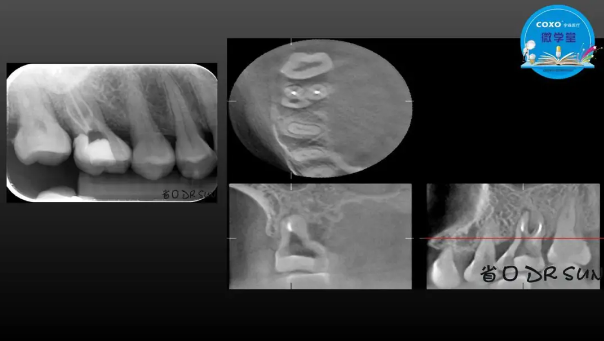

主講:孫書昱

主任醫(yī)師,牙體牙髓副主任, 廣東省口腔醫(yī)院牙體牙髓科 主任醫(yī)師。2003年碩士研究生畢業(yè),研究方向?yàn)檠荔w牙髓病學(xué),擅長(zhǎng)于牙體牙髓病的診斷、齲齒、牙髓炎、根尖周病的治療以及前牙美容修復(fù)。